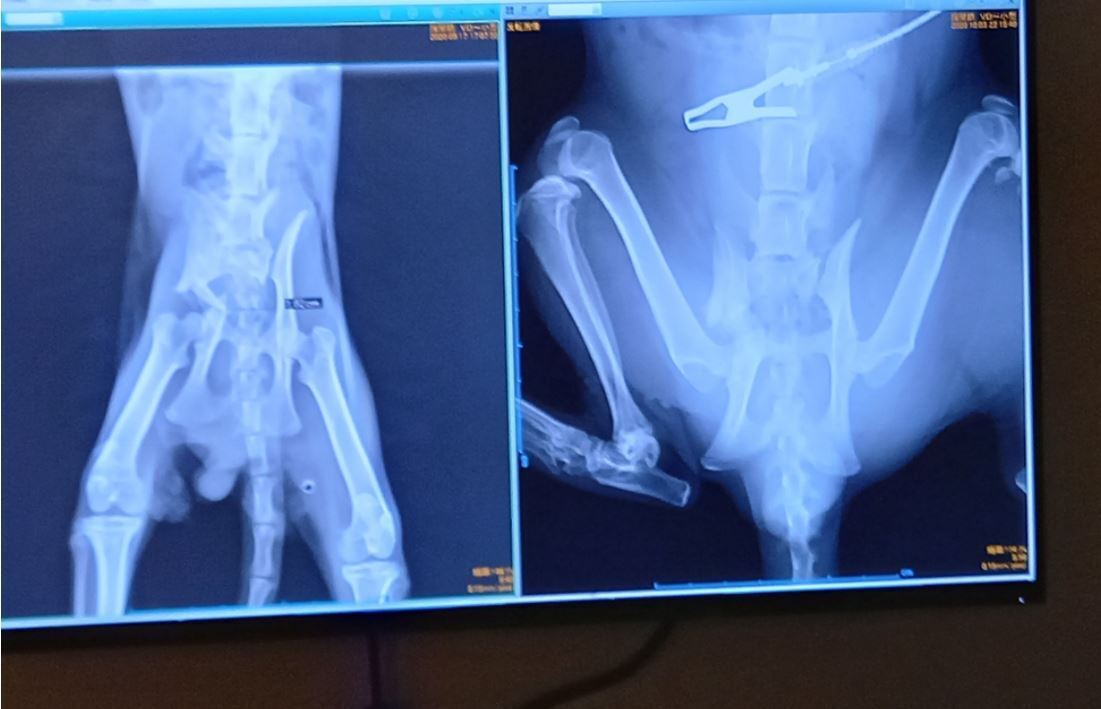

骨盤とうしろあしのレントゲン 左9/16 右10/6

右骨盤の骨が折れてまがっていたのが、若干なだらかにまっすぐになってきている

骨盤右に傾いていたのがまっすぐに

レントゲンを再度撮ってみると、自然な治癒力で治ってきているそうで、何回か必要な大変な手術しないで済むそうです

筋肉が落ちたおかげで、骨がもとに戻ろうとする力が少しずつはたらいているそうです